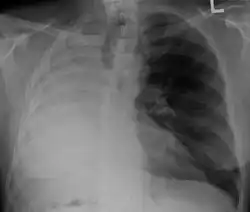

Left tension pneumothorax with a large, well-demarcated area devoid of lung markings with tracheal deviation and movement of the heart away from the affected side.

Tension pneumothorax

Tension pneumothorax is an emergent condition in which air gets trapped in the space between the chest wall and the lung. This space is referred to as the pleural space. Because air can't escape from this space, the air pocket grows larger and larger, resulting in the lung collapse closest to the pneumothorax. Forces are transmitted to the mediastinum and effectively "push" the mediastinal structures to the opposite side of the chest.[5]